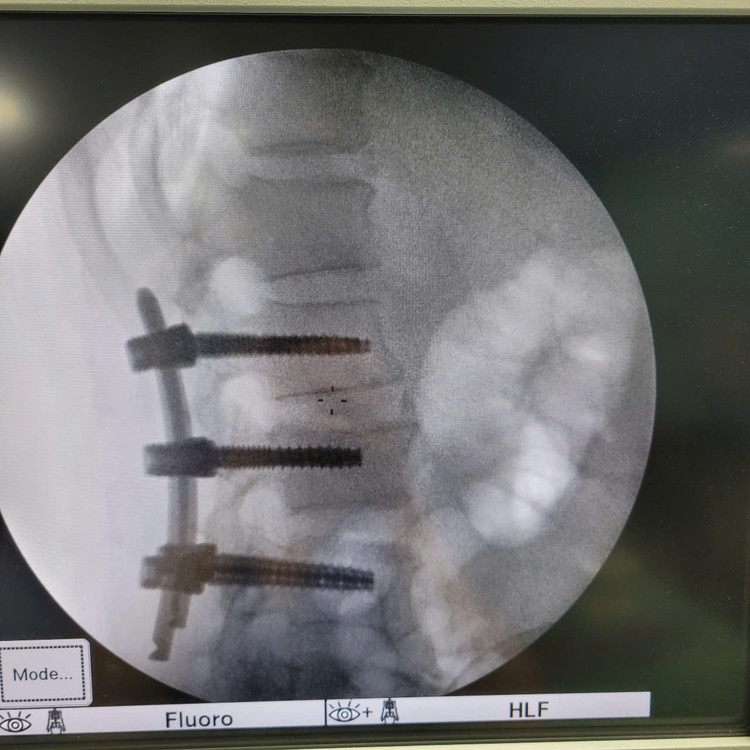

bat-vit-5639.jpg

Ca phẫu thuật cho bệnh nhân - Ảnh BVCC